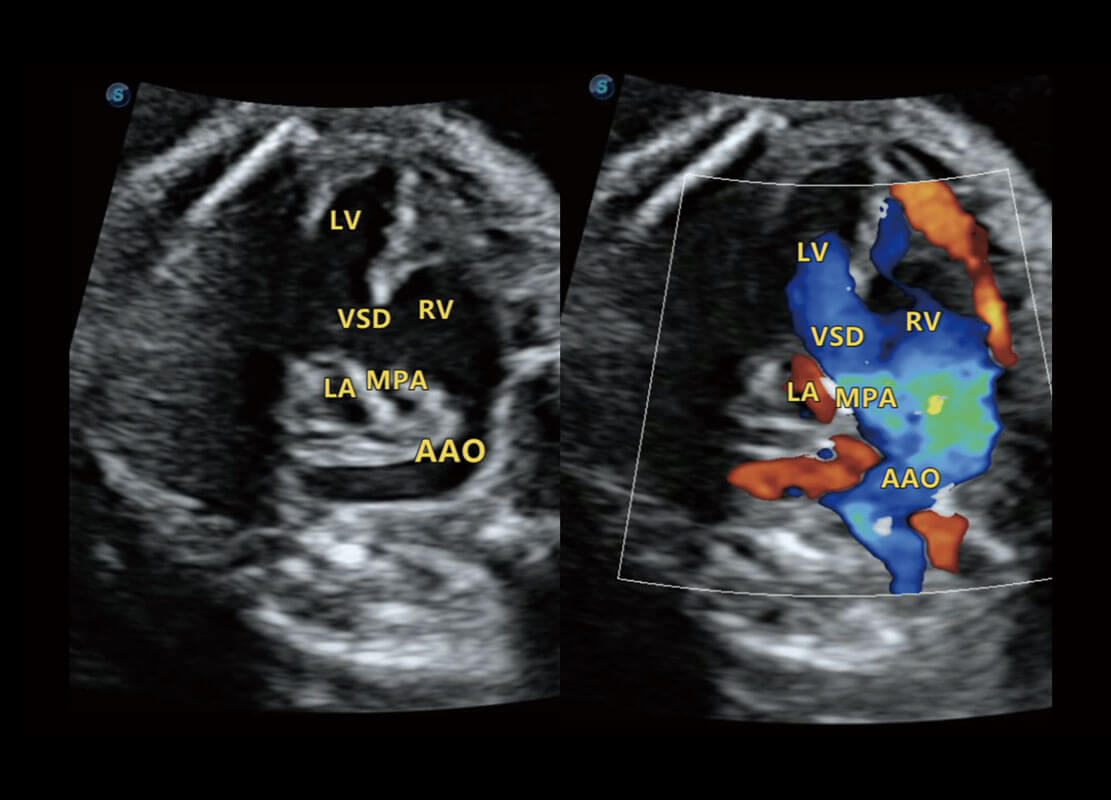

胎心筛查

P60搭载一系列胎儿心脏成像技术,实现精细的胎儿心脏评估。

• 右室双出口